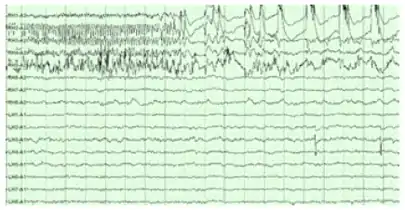

Electroencephalography

The hippocampus shows two major "modes" of activity, each associated with a distinct pattern of neural population activity and waves of electrical activity as measured by an electroencephalogram (EEG). These modes are named after the EEG patterns associated with them: theta and large irregular activity (LIA). The main characteristics described below are for the rat, which is the animal most extensively studied.[82]

The theta mode appears during states of active, alert behavior (especially locomotion), and also during REM (dreaming) sleep.[83] In the theta mode, the EEG is dominated by large regular waves with a frequency range of 6 to 9 Hz, and the main groups of hippocampal neurons (pyramidal cells and granule cells) show sparse population activity, which means that in any short time interval, the great majority of cells are silent, while the small remaining fraction fire at relatively high rates, up to 50 spikes in one second for the most active of them. An active cell typically stays active for half a second to a few seconds. As the rat behaves, the active cells fall silent and new cells become active, but the overall percentage of active cells remains more or less constant. In many situations, cell activity is determined largely by the spatial location of the animal, but other behavioral variables also clearly influence it.

The LIA mode appears during slow-wave (non-dreaming) sleep, and also during states of waking immobility such as resting or eating.[83] In the LIA mode, the EEG is dominated by sharp waves that are randomly timed large deflections of the EEG signal lasting for 25–50 milliseconds. Sharp waves are frequently generated in sets, with sets containing up to 5 or more individual sharp waves and lasting up to 500 ms. The spiking activity of neurons within the hippocampus is highly correlated with sharp wave activity. Most neurons decrease their firing rate between sharp waves; however, during a sharp wave, there is a dramatic increase in firing rate in up to 10% of the hippocampal population